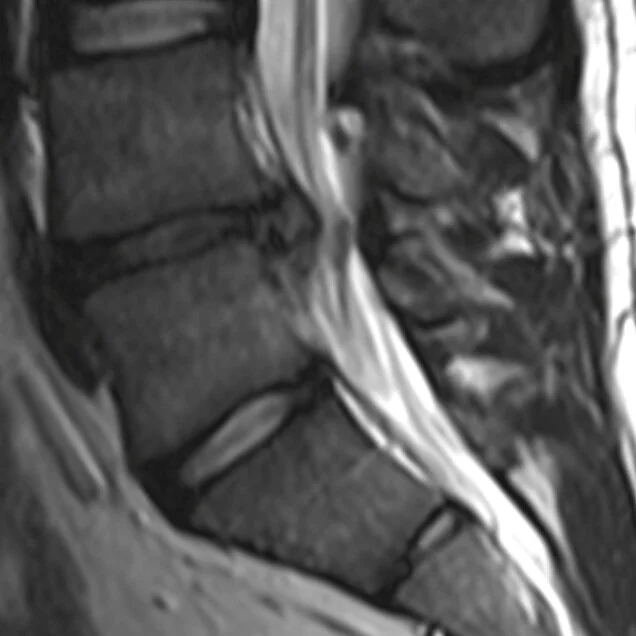

CONDITIONS À LA COLONNE VERTÉBRALEAyant débuté sa carrière au Spine Institute, les douleurs au dos et au cou restent les conditions les plus traitées par Physio Steve..

Ayant débuté sa carrière au Spine Institute, les douleurs au dos et au cou restent les conditions les plus traitées par Physio Steve..